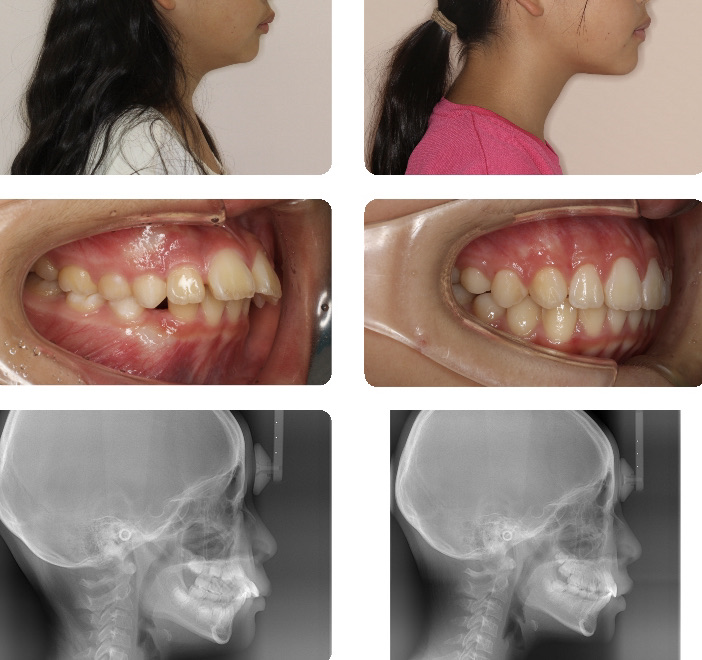

上顎前突

本症例はヘッドギアにて上顎前歯を後退するスペースを獲得した後、上顎前歯を整列しました。その後バイオネーターにて下顎の発育を促し、上下顎の前後的なバランスを改善しました。装置の使用には非常に協力的であったため、良好な結果が得られました。

1期治療が功を奏し、2期治療は必要ないところまで改善できました。